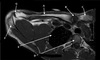

Perfectly

4

Q

What is letter B?

A

DELTOID MUSCLE

How well did you know this?

1

Not at all

2

3

5